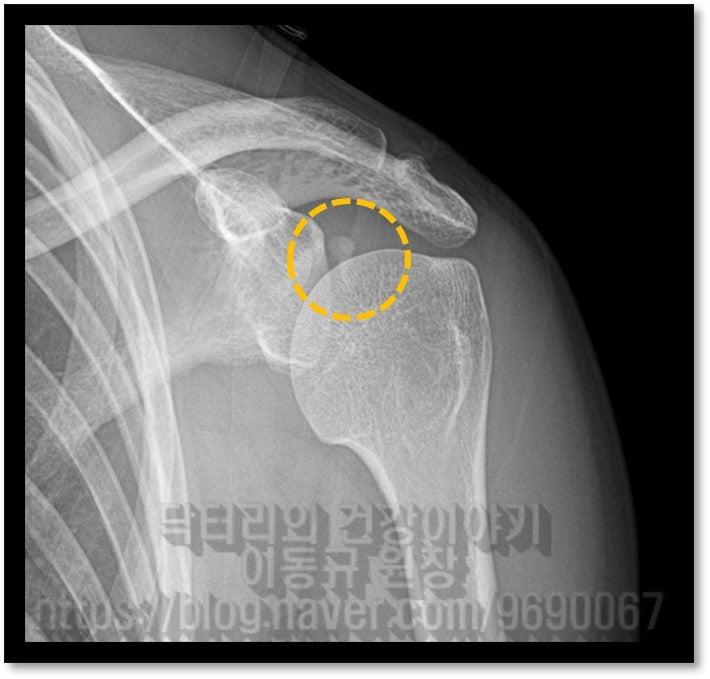

석회성 건염은 매우 통증이 심한 질환입니다. 대부분 회전근개 내에 발생되는 경우가 많습니다. 힘줄에 발생하게 되면 해당 힘줄을 움직일때 마다 극심한 통증을 유발하게 됩니다. 그런데 이러한 석회성 건염이 힘줄이 아닌 다른 곳에 발생된다면 어떨까요? 이번 케이스는 43세 여자 환자 분으로 평상시 피트니스 모델 및 대회를 나갈 정도로 운동을 활발히 하시는 분입니다. 2년전부터 어깨 통증이 발생되고 어깨 후방, 어깨 죽지로 통증이 심하게 있었던 분입니다. 마치 증상이 목 디스크로 인한 연관통 처럼 보이기도 하고 흉곽터널증후군 처럼 보이기도 합니다. 환자는 타 병원에서 목, 어깨 MRI 까지 촬영을 했지만 특별한 진단을 받지 못하고 경추부 문제 정도로 보인다는 이야기를 듣고 주사치료 및 도수치료만 받아오셨던 분이었습니다. 하지만 증상의 호전이 보이지 않고 점점더 통증이 심해지고 근력이 약해져서 저한테 내원하셨던 분이었습니다. 우선 이학적 검사를 해 보았습니다. 특별히 이학적 검사상 특이 소견을 보이지는 않았으나 biceps load test, O'brien test, E/R test 양성 소견을 보였습니다. 즉, 관절와순 병변이 의심되는 소견이었습니다. 가지고 온 영상 자료를 살펴 보겠습니다.

경추부 X-ray 와 MRI 도 확인했으나 특이소견은 없었습니다. 즉 이 환자분은 조금 특이한 위치에 석회가 있으면서 어깨 통증을 유발된 환자고 위치적으로 상견갑신경과 비슷한 위치에서 염증을 일으키다 보니 경추부 문제로 오진되어 치료를 제대로 받지 못했던 경우로 판단됩니다. 위치적으로 뉴핌스치료(석회분쇄흡입술)을 할 수 없는 위치이며 상부관절와순 손상에 대한 치료를 동시에 하기 위해 수술적 치료를 결정하였습니다.